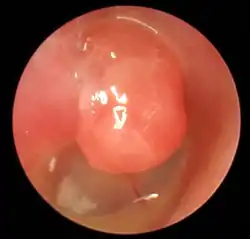

Großes Attikcholesteatom (Pfeil), linkes Ohr

• Retraktionscholesteatom: Ursprung des Cholesteatoms ist die Bildung einer sogenannten Retraktionstasche im Bereich der Pars flaccida (Shrapnell’sche Membran) des Trommelfells im obersten Teil des Trommelfells, vermutlich durch eine chronische Störung der Tubenventilation. Das Cholesteatom entwickelt sich aus der Retraktionstasche und breitet sich vorerst im Kuppelraum des Mittelohres (Attik) aus; man nennt dieses Cholesteatom daher auch Attikcholesteatom.